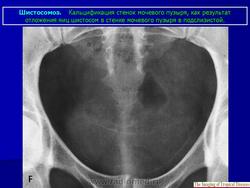

Бильгарциоз (Schistosomiasis) мочевого пузыря